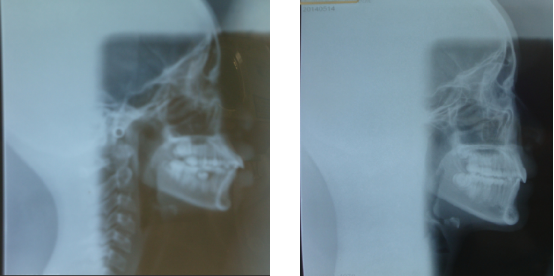

矫正前后X光图对比